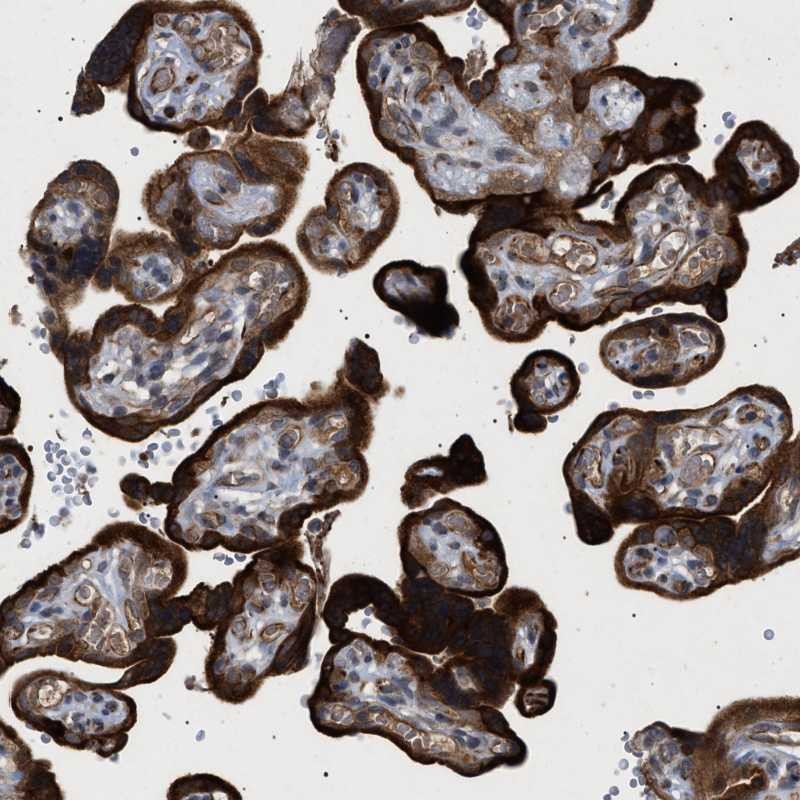

Immunohistochemical staining of human placenta shows strong cytoplasmic positivity in trophoblastic cells.